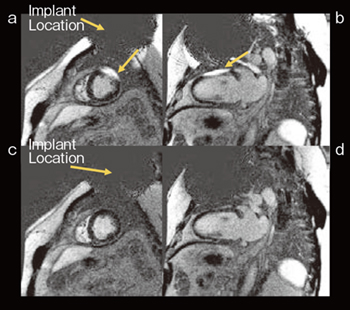

近年のcardiac implantable electronic devices(CIEDs)の技術進歩により,環境電磁干渉に対する耐性が向上し,多くの最新モデルが「MR条件付き(MR Conditional)」デバイスとして認可されている。CIEDsを装着した患者の数は増加しており,左室駆出率(LVEF),左心室容積,心筋瘢痕の正確な評価のために心臓MRIの需要が高まっている。CIEDsのジェネレータは一般的に左上胸部に埋め込まれており,バッテリーや電子部品の影響によって局所的にB0(静磁場)およびB1(RF磁場)の歪みや信号損失が起こり,診断困難な画像が生成されることがある。GEHCのMRIでは,以前より広帯域RFによるbroadband adiabatic IRパルスが採用されており,インプラントによって引き起こされるアーチファクトの影響を低減し,遅延造影の画質改善が図られている(図3)。

図3 Broadband adiabatic IRパルスによるアーチファクト低減

従来の遅延造影短軸像(a)と長軸像(b)。broadband adiabatic IRパルスによる遅延造影短軸像(c)と長軸像(d)。broadband adiabatic IRパルスにより,CIEDsの影響によるアーチファクトが低減されている。